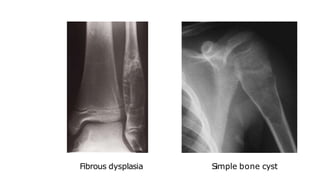

Fibrous dysplasia

 May affect one or several bones.

 Affects the long bones and ribs as a well defined lytic lesion

and may expand the bone.

 T

here may be a sclerotic rim around the lesion.

Simple bone cyst

 Has a wall of fibrous tissue and is filled with fluid.

 I

t occurs in children and young adults, most commonly in

the humerus and femur

.

he cortex may be thin and the bone expanded.

 Pathological fracture.

Fibrous dysplasia Simple bone cyst